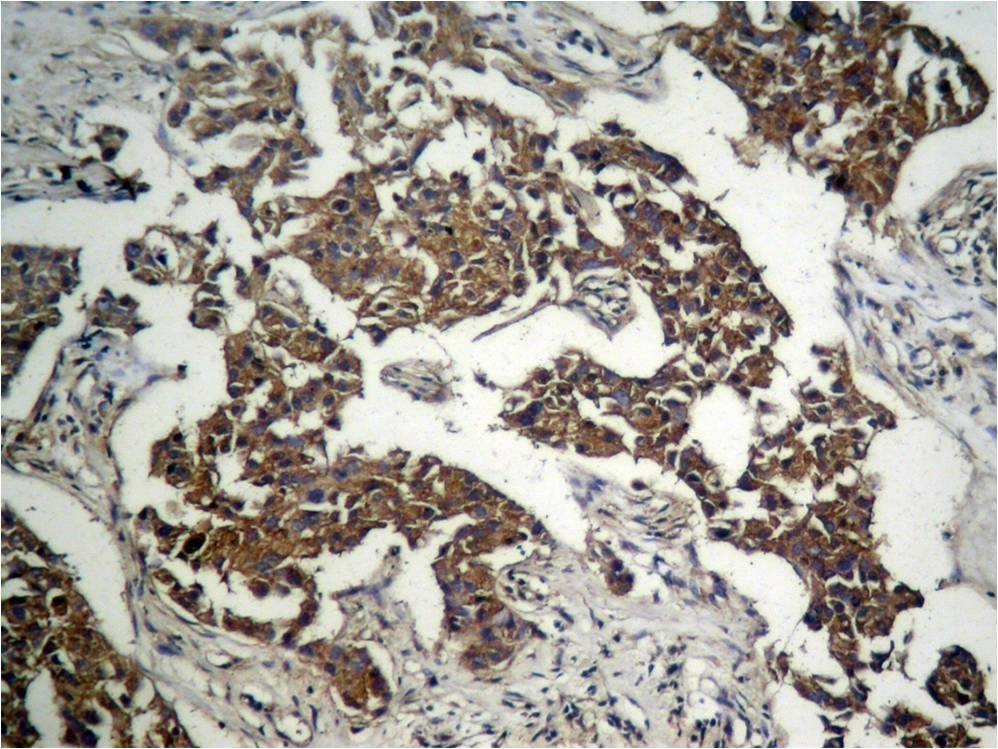

Immunohistochemical analysis of paraffin-embedded human breast carcinoma tissue using GSK3β (Phospho-Ser9) Antibody P40002 (left) or the same antibody preincubated with blocking peptide (right).

Immunohistochemical analysis of paraffin-embedded human Lung carcinoma tissue using GSK3β (Phospho-Ser9) Antibody P40002.